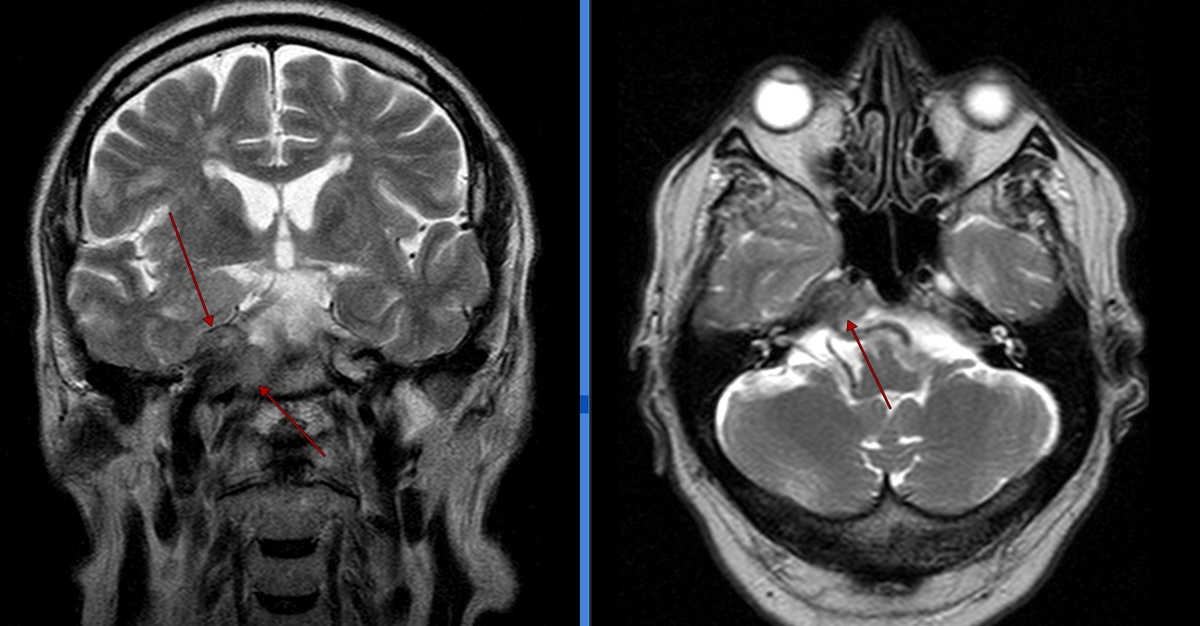

Рис.1. Т2-ВИ корональная и аксиальная плоскость (слева направо): В области правой Меккелевой цистерны и правых отделах ската определяется объемное образование с признаками муфтообразного охватывания С3, С4 сегментов внутренней сонной артерии.